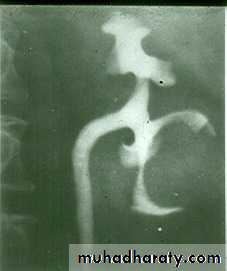

• IVU: Early stage –cobble stone Later filling defects due to graneulomatos papilloma Carcinoma is important complication Ureters : dilated and tortuousIn early stage hydroureter and hydronephrosis + refluxSPACE OCCUPING LESION